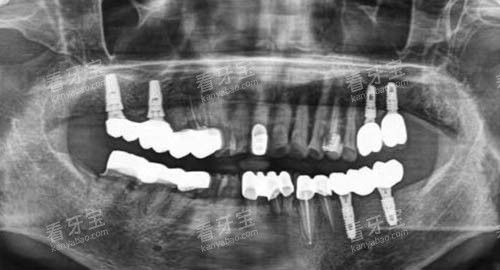

在口腔检查方面,配备了智能化口腔全景机、口腔CT等设备。

这些设备能够清晰地显示牙齿和口腔组织的结构,帮助医生比较准诊断病情。

智能化口腔全景机可以一次性拍摄全口牙齿的影像,为医生提供超全的信息;口腔CT则能够提供三维立体的图像,让医生更直观地了解牙齿的情况,制定更比较准的治疗方案。